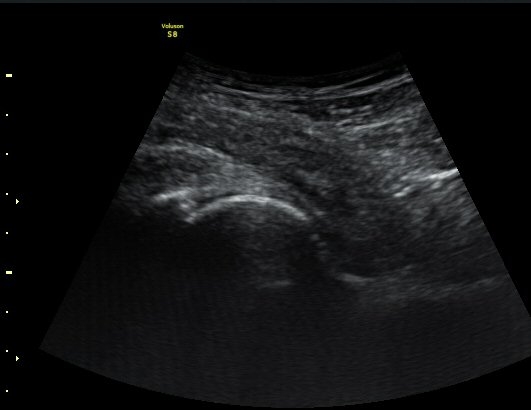

¼±»óŽÃÊÀÚ¸¦ ÀÌ¿ëÇÑ °Ë»ç¿¡¼­ ÀüÇÏÀ屨ÀÇ ´ëÅðÁ÷±Ù ±â½ÃºÎ¿¡ ¼®È¸È­ À½¿µÀÌ ¶Ñ·ÈÈ÷

°üÂûµÊ(»çÁø 4, 5).